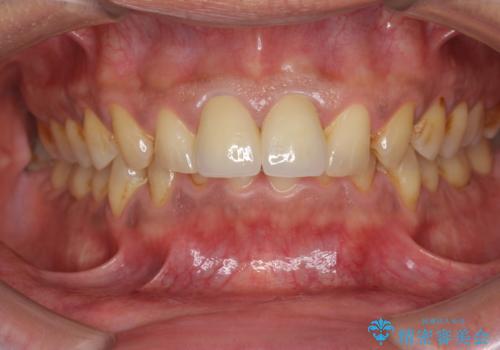

歯ぐきからの出血 膿が出る 前歯根管・セラミック治療

- 40代男性

- 体調により前歯部の歯ぐきから出血や膿が出ることの改善を求めて来院されました。

X線写真より、根尖部に透過像が認められ根管治療・ファイバーコア築盛・セラミッククラウンの作製が必要な状態です。